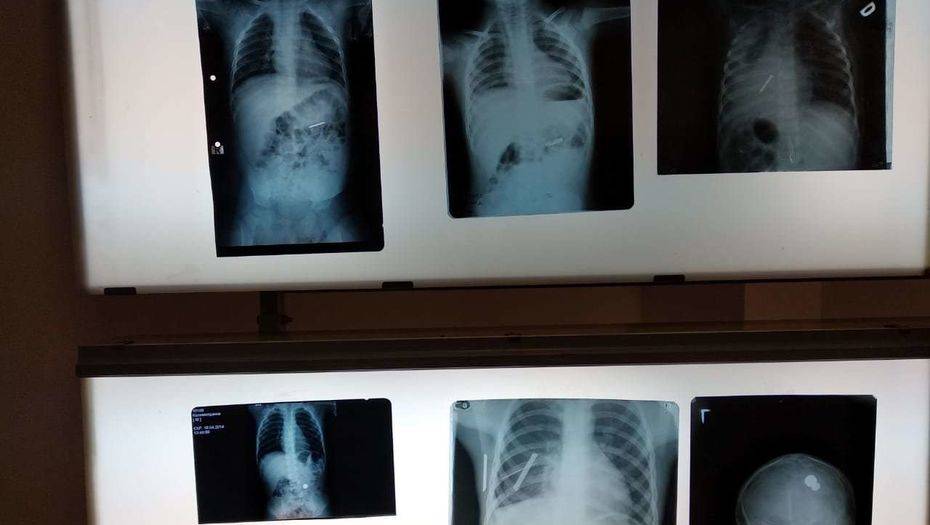

Сотни инородных предметов ежегодно извлекают медики во время операций из тел детей, сообщил главный врач городской детской больницы №2 Астаны Биржан Досмаилов.

"Сейчас очень наболевшая проблема среди детей – это попадание инородных тел в естественные отверстия: бронхо-лёгочную систему, желудочно-кишечный тракт, нос, уши. За 2017 год отмечалось 30 случаев попадания инородных предметов в дыхательные пути и за 10 месяцев 2018 года – 27 случаев", – сказал Биржан Досмаилов на брифинге для журналистов.

В прошлом году в столичную больницу попали 129 детей, проглотивших различные предметы, за 10 месяцев 2018 года – 131 случай.

"Особо опасными являются магниты. У нас были случаи, когда ребёнок проглотил и думает, что с помощью второго магнита сможет достать первый и глотает до 10-12 магнитов. И в желудочно-кишечном тракте они слипаются, что может привести к некрозу и развитию перитонита", – добавил Досмаилов.